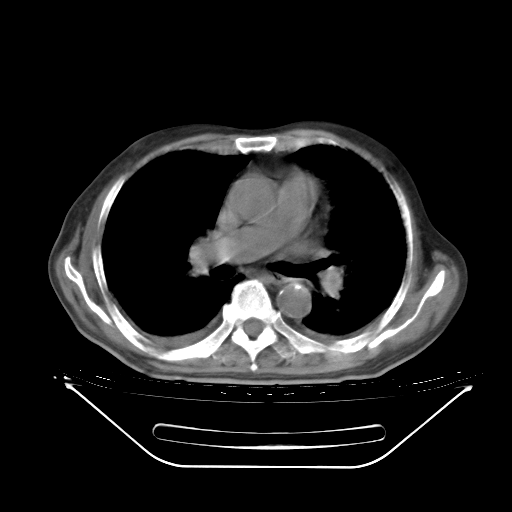

今天复查肺部CT,发现双肺广泛磨玻璃样改变。所以我把3月19日和5月9日相隔50天的肺部CT上传。请大家会诊。

5月9日肺部CT(在4月27日齐鲁医院肺部CT描述部分肺组织磨玻璃样改变,12天后肺组织广泛磨玻璃样改变)

2009年5月9日肺部CT

大致读了系列胸部CT:纵隔窗无明显异常,肺窗:从4、27至今:主要是双肺中下野外带可见毛玻璃样改变,目前处于急性肺泡炎阶段,至于原因考虑1、结替组织或胶原血管性疾病所致?2、恶性疾病如恶组在肺部所致的表现或细支气管肺泡癌?3、药物或其它原因如肺蛋白沉着症所致肺泡炎目前不太可能?总之,明天就去请我院的呼吸科、感染科、血液科和临免专家会诊哈。